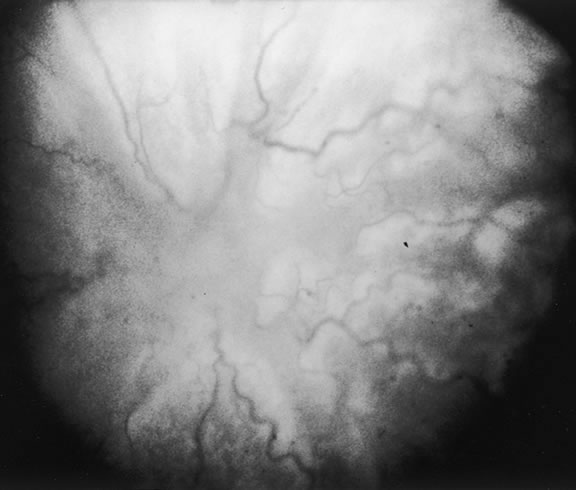

The nature of the adhesion between the vitreous cortex and the ILM is enigmatic. This adhesion is strongest at the optic nerve, the macula, the vitreous base, and retinal vessels. Foos6 demonstrated attachment plaques between Müller's cell cytoplasm and the ILM in the basal and equatorial retina (Fig. 2). Vitreous traction mediated by vitreous fibrils may contribute to these adhesions. These attachment plaques are not present posterior to the equator except where the ILM is thinned in the fovea. This anatomic variation in the fovea region may play a role in the pathogenesis of some of the vitreomacular disorders.

The ILM also thins over major blood vessels. Vitreous strands extend through pores in the ILM to surround the vessels11 and have been termed vitreoretinovascular bands.12 These bands may explain the strong adhesion between the vitreous and retinal vessels.

Despite the presence of these anatomic interfaces between the vitreous cortex and ILM, the adhesion of these structures is still poorly understood. Biochemical investigations suggest that vitreoretinal adhesion involve molecular adhesion mediated by glycoproteins such as fibronectin, laminin, and other glycoconjugates. The ILM consists of type IV collagen, laminin, fibronectin, type I collagen, and as yet uncharacterized glycoproteins. It is believed these substances mediate vitreoretinal adhesion.13